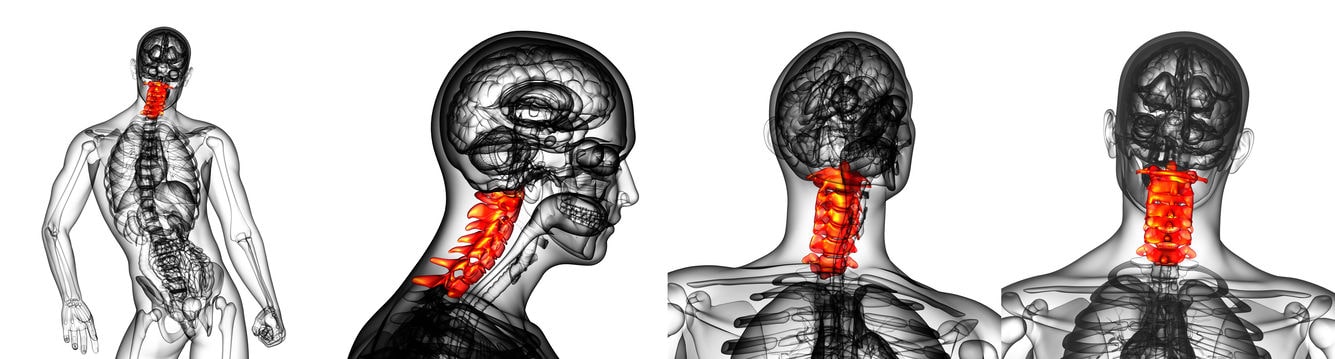

Operación de cervicales

Última actualización el 23 enero 2024 a las 12:53...